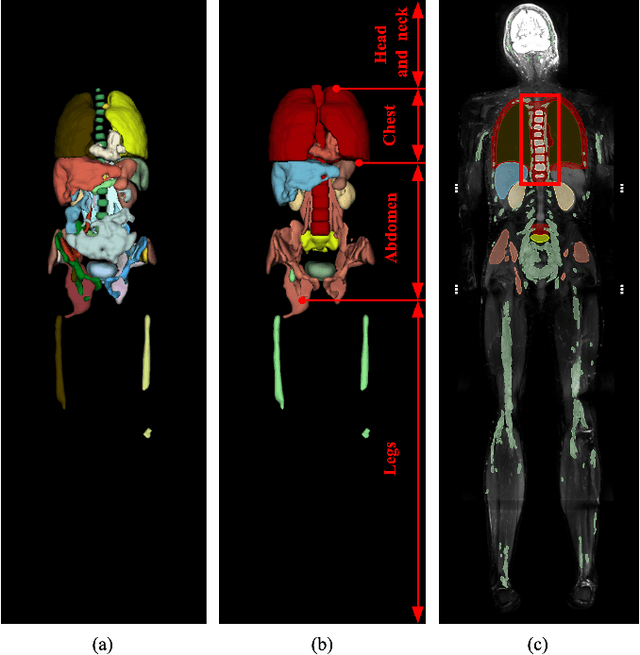

Abstract:Neurofibromatosis Type 1 is a genetic disorder characterized by the development of neurofibromas (NFs), which exhibit significant variability in size, morphology, and anatomical location. Accurate and automated segmentation of these tumors in whole-body magnetic resonance imaging (WB-MRI) is crucial to assess tumor burden and monitor disease progression. In this study, we present and analyze a fully automated pipeline for NF segmentation in fat-suppressed T2-weighted WB-MRI, consisting of three stages: anatomy segmentation, NF segmentation, and tumor candidate classification. In the first stage, we use the MRSegmentator model to generate an anatomy segmentation mask, extended with a high-risk zone for NFs. This mask is concatenated with the input image as anatomical context information for NF segmentation. The second stage employs an ensemble of 3D anisotropic anatomy-informed U-Nets to produce an NF segmentation confidence mask. In the final stage, tumor candidates are extracted from the confidence mask and classified based on radiomic features, distinguishing tumors from non-tumor regions and reducing false positives. We evaluate the proposed pipeline on three test sets representing different conditions: in-domain data (test set 1), varying imaging protocols and field strength (test set 2), and low tumor burden cases (test set 3). Experimental results show a 68% improvement in per-scan Dice Similarity Coefficient (DSC), a 21% increase in per-tumor DSC, and a two-fold improvement in F1 score for tumor detection in high tumor burden cases by integrating anatomy information. The method is integrated into the 3D Slicer platform for practical clinical use, with the code publicly accessible.